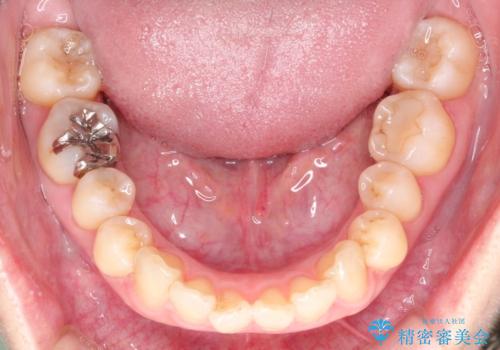

【インビザライン 】前歯を下げたい

- 前歯の凸凹と、前突を主訴に来院されました。

インビザライン にて治療を行なっております。